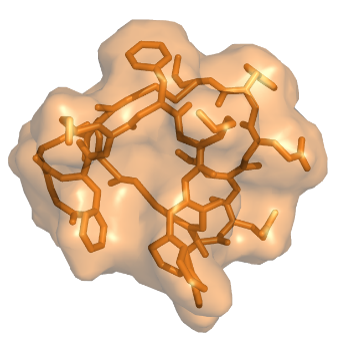

Our Trilomer® platform of mirror-image cyclic peptides enables the targeted delivery of potent chemotherapy drugs for the treatment of cancer.

Trilomer® mirror-image drug-conjugates overcome the liabilities of ADCs and peptide-drug conjugates by using 100% D-amino acids, which inherently possess high resistance to proteases (preventing premature release of chemotherapy drug) and also exhibit low uptake by renal scavenger receptors (reducing toxicity to healthy tissues and organs).

Trilomer® drug-conjugates rapidly penetrate tumors and bind specifically to cell-surface proteins on cancer cells, after which they are rapidly internalized, releasing the chemotherapy drug directly inside the cancer cell.

✦ targeted delivery of payloads: small size (<6 kDa for bivalent binder plus payload) allows for rapid tumor/tissue penetration

• overview of mirror-image peptides:

"D-Peptide and D-Protein Technology: Recent Advances, Challenges, and Opportunities"

Chembiochem. 2023 Feb 14;24(4):e202200537. PMID: 36278392

Peptides made from 100% D-amino acids

Large binding surface allows targeting

to any cell-surface protein